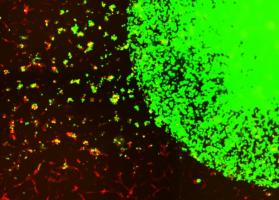

AVC et THÉRAPIE CELLULAIRE : Les cellules souches savent trouver leur chemin

Actualité publiée le 19/03/2026AVC : La thérapie cellulaire qui reste efficace longtemps après